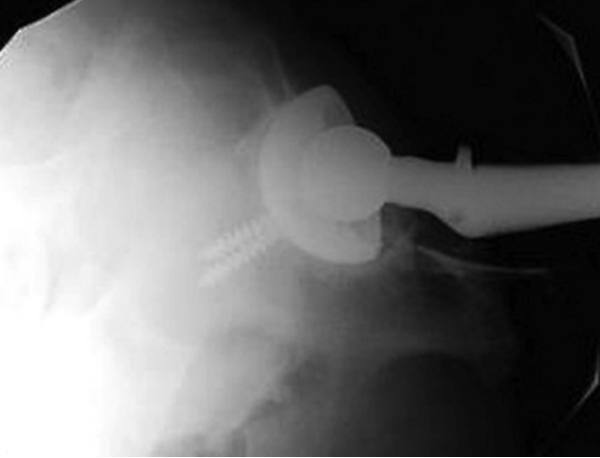

describe the position of the acetabular cup?